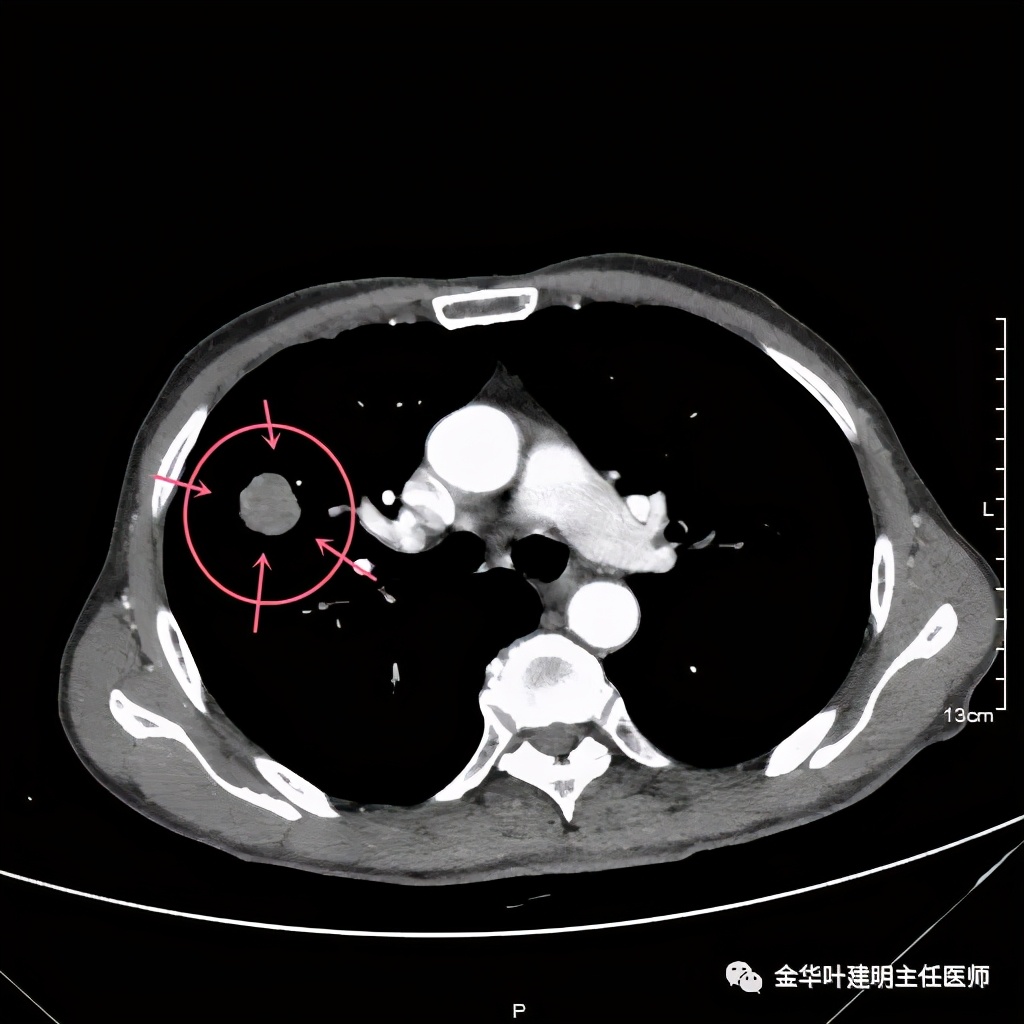

上图黄色箭头示穿刺针进入的地方,位置还是非常好的,应该容易穿到有价值的病变组织。但穿刺结果未见肿瘤:

病理不支持!怎么办?是抗炎治疗了先出院随访,还是仍手术?如果穿刺阴性仍予以手术,感觉穿刺失去了价值;如果不手术放回去,这样影像表现的病灶能放心认为是慢性炎吗?患者家属找到我,问我的意见,应该如何。我们先再来看看病灶的影像细节:

上图是穿刺时的某个层面,病灶的细毛刺征比较明显(蓝色箭头),病灶的边缘是不平的,而且有细短的毛刺样突向周围肺组织,这可是恶性的特征

上图紫色箭头示明显的叶间胸膜牵拉,红色箭头示病灶,中间还有空腔,边缘有细毛刺,感觉上病灶就是有收缩力而僵硬的

上图示病灶强化不等,表现不平,中间有空洞,空洞旁边有偏低密度区(坏死?)

上图示病灶膨胀分叶,表面不平,像个土豆

上图黄色箭头示空洞形成,病灶表面不平